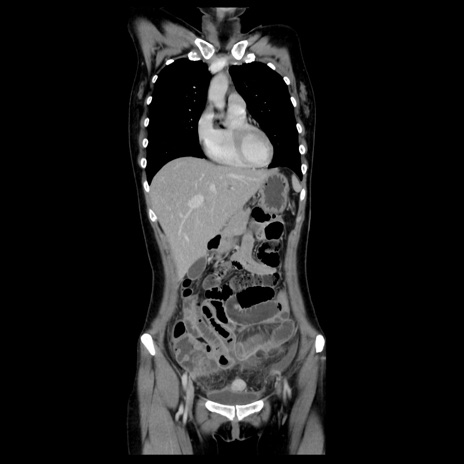

症例39(冠状断像)

【症例】40歳代女性

【主訴】上下腹部痛

【現病歴】2日目から下腹部痛あり。夜間は痛みで眠れなかった。昨日より上腹部痛と下痢が出現。臥位で痛みは軽快したため、休んでいた。本日になって臥位でも立位でも痛みが強くなってきたため救急要請。

【既往歴】子宮内膜症

【身体所見】部:平坦・軟、左上下腹部に圧痛あり、反跳痛あり。

【データ】WBC 21800、CRP 26.78

CT